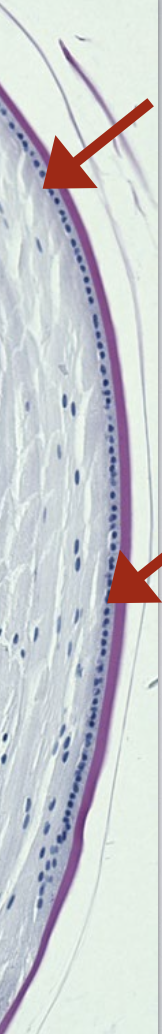

What are the key histological features of the lens capsule?

Lens capsule - true PAS-(+) BM

varies in thickness (thickest anteriorly & thinnest at the posterior pole)

has a very slow turnover (months to years)

made up of 2 lamina (layers) that can separate under certain disease conditions

Where is the lens epithelium located?

found just under the lens capsule, on the anterior ½ of the lens

no epithelium on the posterior surface of the lens

Anteriorly: capsule → epithelium → lens fibers

Posteriorly: capsule → lens fibers directly (no epithelium)